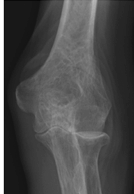

Figure 62-3 A: Stage II rheumatoid arthritis. B: Stage II rheumatoid arthritis.

Figure 62-4 A: Stage III rheumatoid arthritis. B: Stage III rheumatoid arthritis.